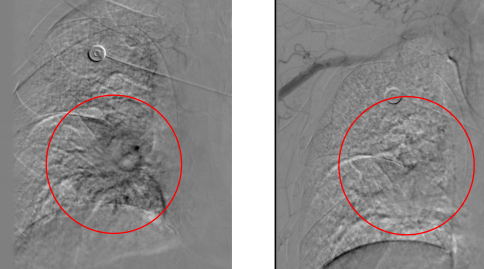

(左图显示右侧见不规则肿瘤染色,栓塞后,右图可见支气管动脉远端未见显影。)

面对病情,患者家属思虑再三,拒绝了抗肿瘤治疗。看着张爷爷痛苦的样子,家人心里像被针扎一样。孙继泽教授告诉他们,考虑到患者的年龄和体力评分不适合常规的抗肿瘤治疗,支气管动脉灌注栓塞治疗是一项先进的微创手术,就像「堵住漏水的水管」一样,能快速止住出血,而且「标本兼治」——控制出血同时截断肿瘤的营养供应,创伤小,恢复快,能最大程度减少老人的痛苦和治疗原发疾病。

止血效果立竿见影,咯血症状明显好转,咳嗽、咳痰的情况也减轻了不少。患者精神状态一天比一天好,脸上渐渐露出了久违的笑容。家属悬着的心终于落了下来。让人惊喜的是,术后第 3 天,老人就顺利出院了。